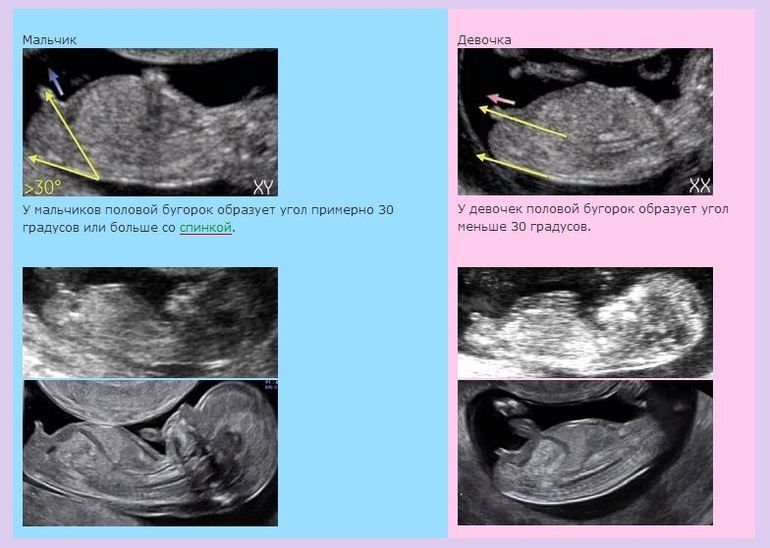

Предположу, что девочка) На первом фото видно вроде как очертания полового бугорка, и мне кажется, что он параллельно спинке идет.

Кристи, ну, насчёт формы черепа не уверена, а вот по половому бугорку могу. Но на ваших снимках его не видно, потому что в основном засняли голову и тело частично.

Светлана , тут плод вообще спинкой развернут. Нужно такое фото, если с 1 скрининга. Изображение Хотя на вашем сроке можно уже увидеть с другого ракурса, со стороны попы.